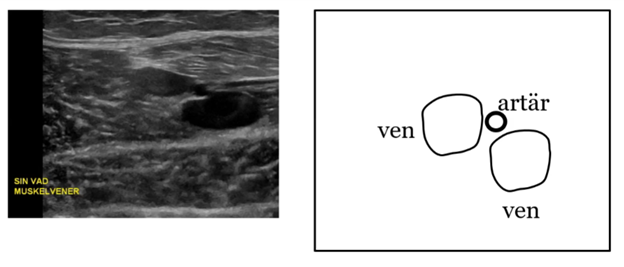

Vad händer med vener och artärer när du trycker transduser emot vävnaden?

Vener trycks ihop men artär hålls öppen